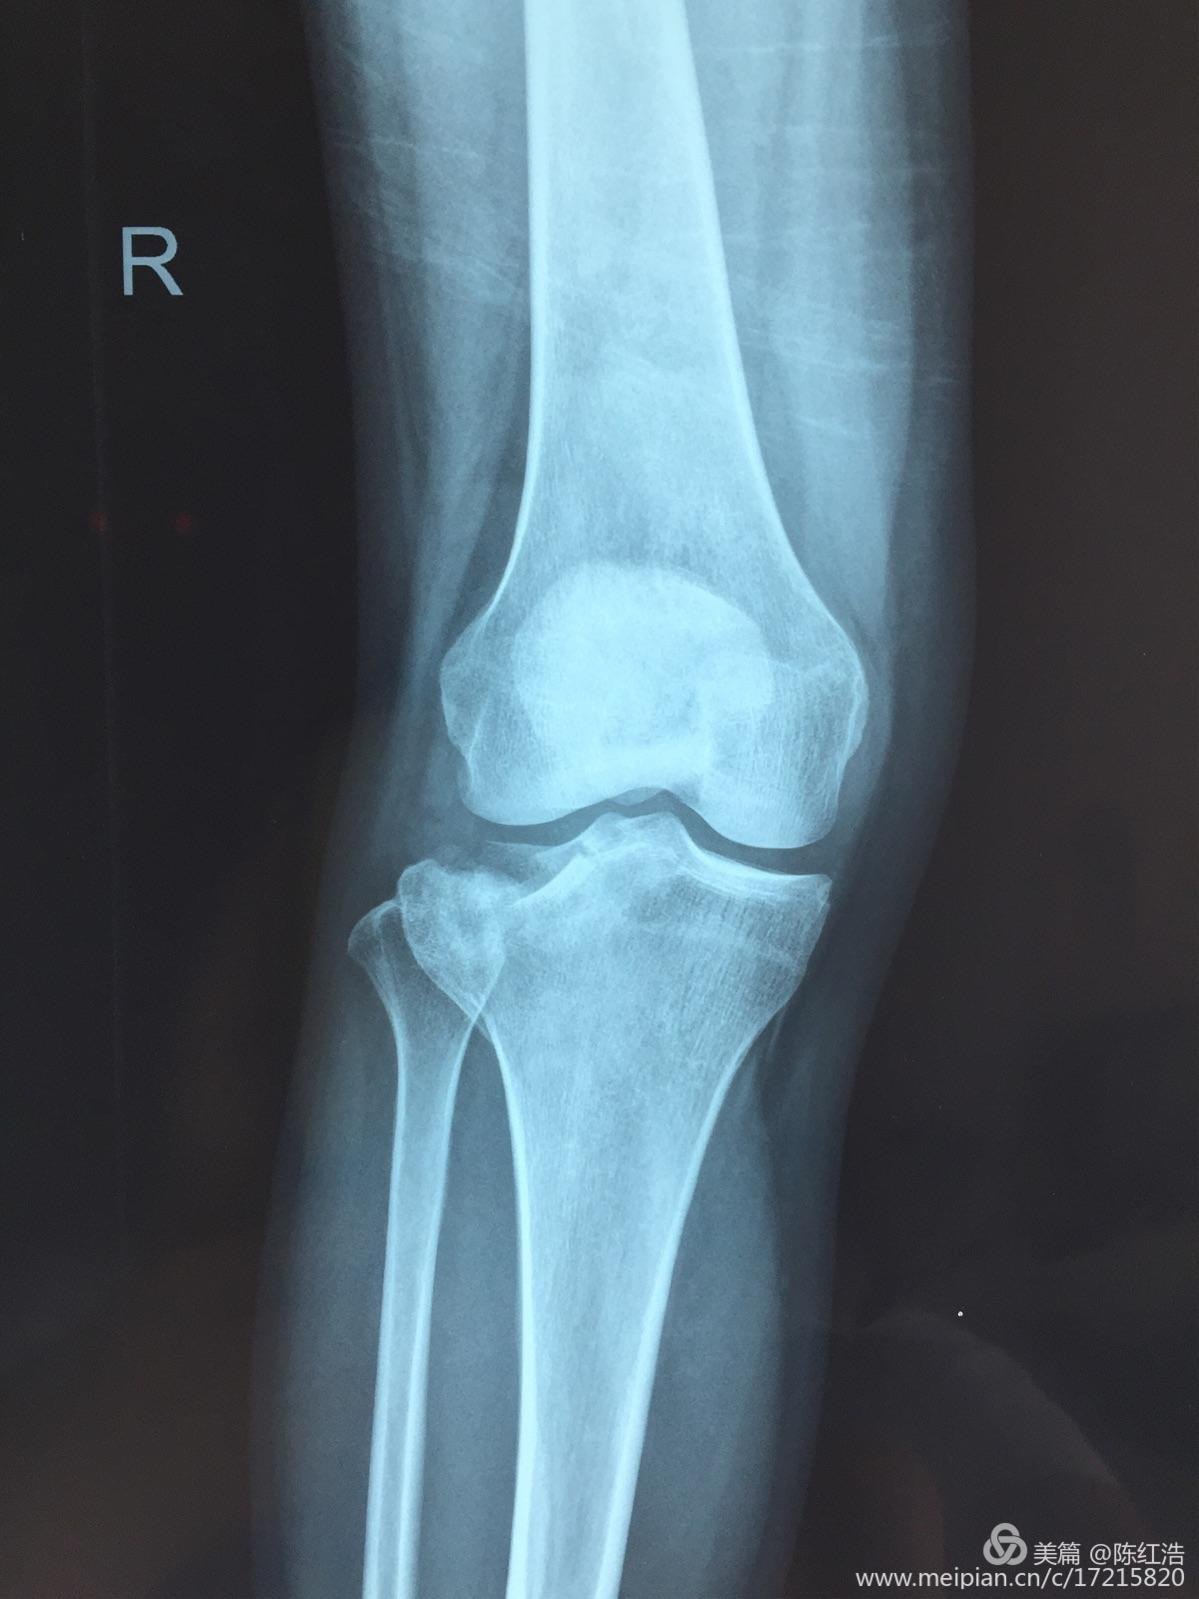

右胫骨平台粉碎性骨折 骨科与显微外科专业讨论版 爱爱医医学论坛

右胫骨平台骨折 胫骨平台骨折 伤感说说吧

右胫骨平台骨折图片 胫骨平台轻微骨裂图片 伤感说说吧

右胫骨平台骨折图片 搜狗图片搜索